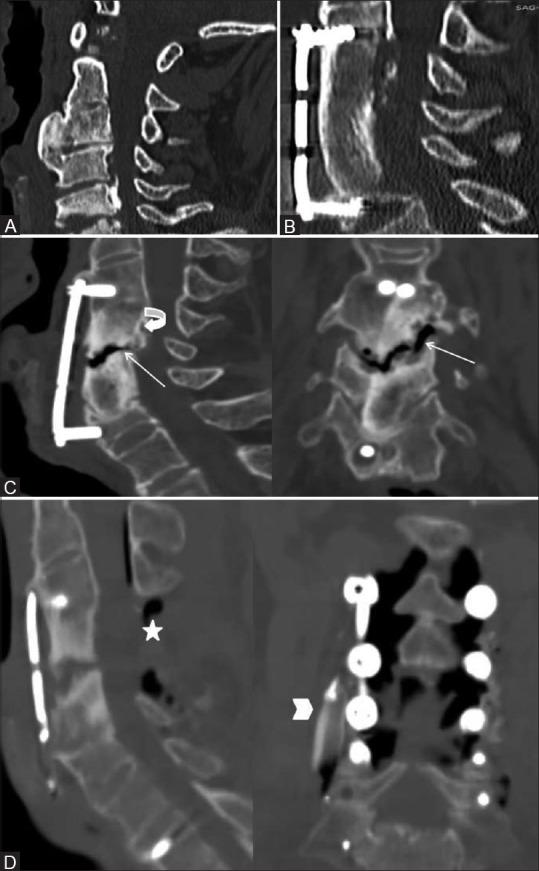

多节段颈椎椎体次全切除术后使用长支撑植骨特有的并发症:先进成像技术的应用

Complications exclusive to long strut grafts used following multilevel cervical corpectomy: Utilization of advanced imaging techniques.

When surgical decompression of cervical spine is considered, multilevel cervical corpectomy with long strut grafts is the preferred treatment. This procedure is used in a variety of pathologies including degenerative disease, tumors, trauma and infection. Corpectomy with interbody grafting helps in adequate spinal canal and neural decompression compared to multilevel discectomy, which could be difficult as well as inadequate. Fibular/iliac strut grafts are used for reconstruction along with a stabilizing hardware in this procedure. So far, complete imaging spectrum of complications exclusive to strut graft has not been reported in the literature. This pictorial essay presents complications exclusive to the strut graft, utility of advanced imaging in diagnosis and a brief note on the clinical management of complications.

摘要

当考虑进行颈椎手术减压时,多节段颈椎椎体次全切除并使用长支撑植骨是首选的治疗方法。该手术适用于多种病理情况,包括退行性疾病、肿瘤、创伤和感染。与多节段椎间盘切除术相比,椎体次全切除并椎间植骨有助于充分减压椎管和神经,因为多节段椎间盘切除术可能既困难又不充分。在此手术中,使用腓骨/髂骨支撑植骨并结合稳定的内固定器械进行重建。到目前为止,文献中尚未报道过支撑植骨特有的完整并发症影像学谱。这篇影像文章介绍了支撑植骨特有的并发症、先进影像学在诊断中的作用以及并发症临床处理的简要说明。